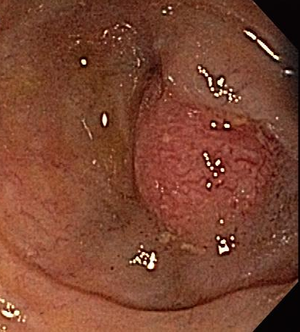

No gallstones were found on RUQ ultrasound in this 45-year-old patient, but a polyp was seen. How would you proceed?